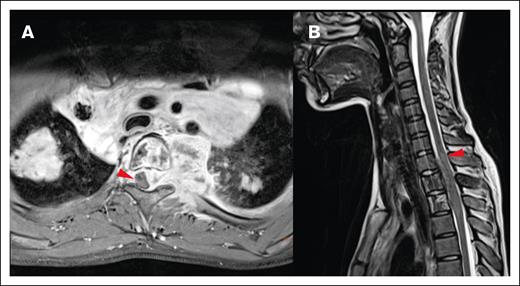

Local impact on CNS structures. (A) Displacement and mild compression of spinal cord to the right without contrast enhancement in the transverse T1 fat saturated image. (B) The same patient with edema clearly visible in the spinal cord in a sagittal T2-weighted MRI image.

Most lesions (92.7%) extended through the neural foramina of either the vertebrae or sacral bone; 2 lesions did not extend through the neural foramina, and 2 lesions could not be evaluated (Figure 4). Thirty-one lesions entered the spinal canal. Of these, 54.8% caused displacement of the spinal cord, 25.8% were adjacent to the spinal cord but did not cause displacement, and 19.4% did not contact the spinal cord (Figure 5). None of the lesions infiltrated into the spinal cord itself. Spinal cord edema was evaluated for patients who had MRI available (17 of 31 lesions). Among these evaluable lesions, only 12.9% had evidence of spinal cord edema.

Most CNS lesions demonstrated an adequate metabolic response at IRA, with 89.1% PET negative (Deauville score 1-3) and 10.9% remaining PET positive (Deauville score 4 or 5; Figure 6). Only 1 of the CNS lesions that remained PET positive at IRA was irradiated, and none of these lesions were sites of relapse. Two CNS lesions (3.6%) that were PET negative at IRA (Deauville 1 and 3) were associated with relapse, and neither received irradiation. Thirteen CNS lesions (23.6%) in 13 patients received irradiation, and none were sites of disease relapse. These results have been summarized in Figure 7.

Staging and response assessment. Imaging at staging shows a large paraspinal mass (A, MRI) with intense glucose metabolism (B, 18F-FDG-PET/CT; red arrows = lymphoma; white arrows = normal kidneys). The mass originates from the bone and extends into the neuroforamen and the spinal canal (A-B). After 2 courses of OEPA chemotherapy, 18F-FDG-PET shows a good metabolic response (C, maximum intensity projection; red circle surrounds the slight residual uptake of the former CNS lesion; [D-E] 18F-FDG-PET/CT; same height as panel B; minimal glucose metabolism within the residual mass [red arrows]).